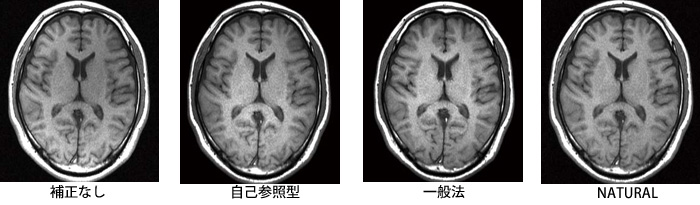

最新の高感度受信コイルは,“RAPID”(パラレルイメージング)対応も含め,マルチチャンネル化が進んでいる。このようなマルチチャンネルコイルは感度が向上する反面,受信感度の均一性においては低下するため感度補正を行う必要がある。例えば,頭部において8チャンネルコイルは,コイルエレメント近傍の頭表部位は高い感度であるが,中心部位では感度が低下し,画像が暗く表現される。そこで,この受信コイルの感度分布をあらかじめ測定しておき,この情報と画像の大まかな明るさ分布をもとに中心輝度を持ち上げる自己参照型補正手法がある。しかしこの手法では,被写体の大きさによる感度分布変化に対応できず,不要な画像ノイズが持ち上がってしまう,病変による信号への影響などの問題がある。

それに対し,ECHELON Vegaに搭載した新たな感度補正手法“NATURAL(NATural Uniformity Realization ALgorithm)”は,図8に示すように,ガントリに内蔵された均一性の高い照射コイルで受信を行い,撮像した参考画像を基準として感度の均一補正を行う技術である。さらにNATURALは,これまでの画像自体で補正を行う自己参照型補正のアルゴリズムも併用することで,より正しい感度補正を行うことができる(図9)。

図9 NATURALの効果

自己参照型:あらかじめ求めた受信コイル感度分布と,画像データの低周波領域から得た輝度傾向を用いて均一補正を行う。

一般法:ガントリコイルの均一な感度分布を基準にして,マルチチャンネルコイルの個々の感度を補正する。

NATURAL:一般法に自己参照型のアルゴリズムも同時に用いて,より正しい補正を行う。